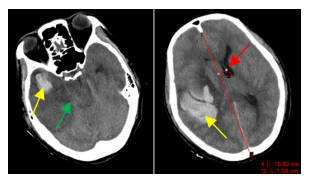

同样是脑动脉瘤,另一位50岁的朱先生就不幸去世了。朱先生因右侧头部持续性疼痛2天,但他认为是最近疲劳未休息好导致,自行服用止痛药治疗,未就诊。家人在凌晨发现其无法被唤醒,入院时已深度昏迷,在我院完善颅脑CT提示大量脑出血,导致脑疝,进一步颅脑CTA明确脑动脉瘤破裂出血(左图)为其病因,经救治还是不幸离世。